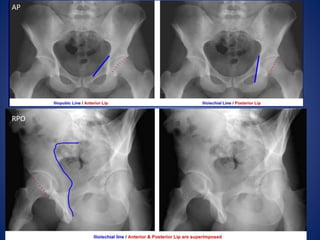

Name the views and the indication for taking

this view…..

Judet Views

Patient supine, oblique patient 45o both ways (RPO & LPO).

Taken to evaluate fractures of acetabulum.

Normal AP view

LPO

AP

RPO